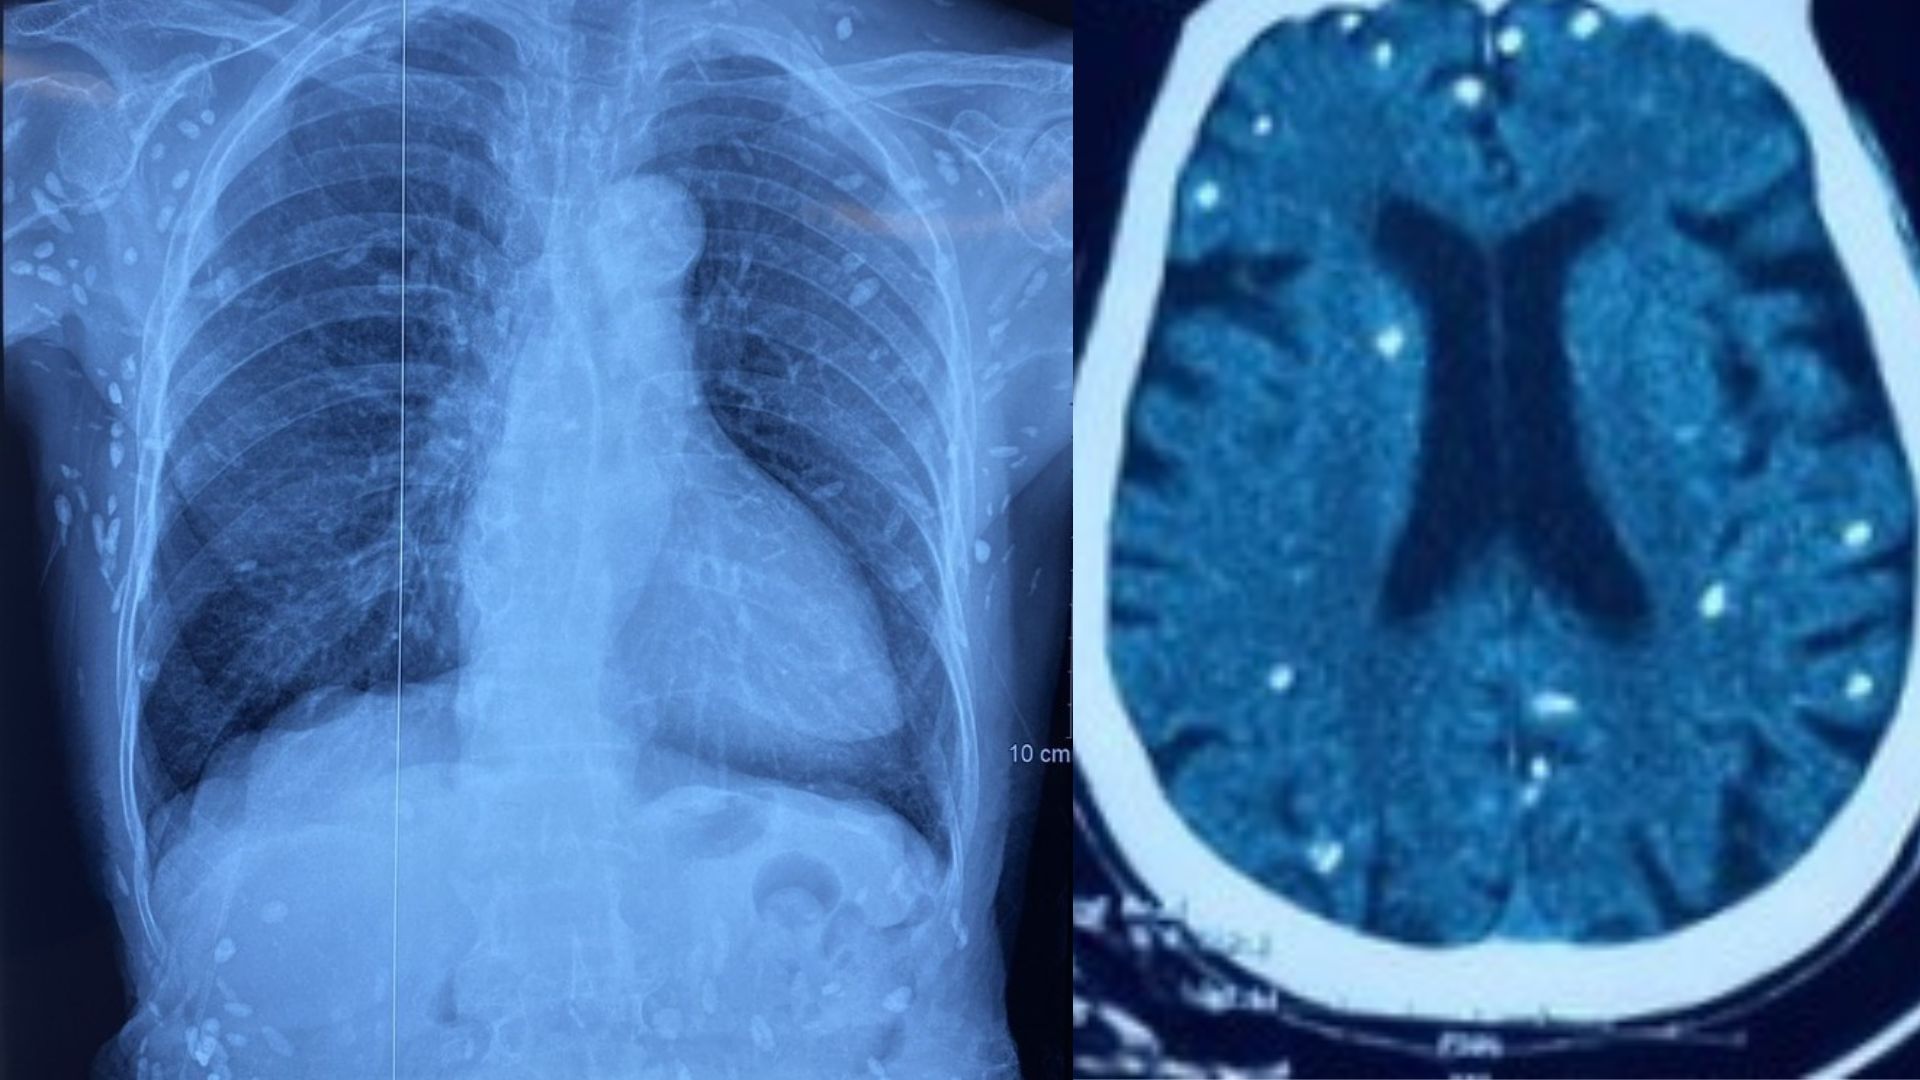

Khi thăm khám, bác sĩ chỉ định nội soi tai mũi họng. Hình ảnh cho thấy xoang lê bên trái có khối u sùi, loét, lan lên gần hố lưỡi thanh thiệt; niêm mạc phù nề. Kết quả sinh thiết cho thấy ung thư biểu mô vảy không sừng hoá. Đây là dạng thường gặp ở ung thư hạ họng, trong đó xoang lê là vị trí phổ biến nhất. Bệnh nhân được chỉ định nhập viện để đánh giá giai đoạn bệnh và lên phác đồ điều trị phù hợp.

Kết quả nội soi có bất thường của bệnh nhân (ảnh BVCC).